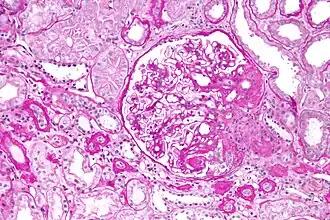

![]() Световая микроскопия нефробиоптата, PAS-реакция. Фокально-сегментарный гломерулосклероз, перихиллярный вариант. | |

При гистологическом исследовании отмечается склерозирование лишь части клубочков, к тому же повреждённые клубочки склерозированы не полностью, а сегментарно, что позволяет провести дифференциальную диагностику с другими клубочковыми заболеваниями почек.

На основании гистологической картины различают такие варианты ФСГС, как[4]:

- Классический — наличие зон склероза и гиалиноза в некоторых сегментах отдельных клубочков, умеренная клеточная пролиферация, адгезия петель клубочков к капсуле с образованием синехий, гипертрофия и вакуолизация подоцитов, отделение их от базальной мембраны клубочка, жировая и белковая дистрофия эпителия канальцев

- Перихиллярный — склерозирование зоны сосудов

- Клеточный — расширение мезангия, гиперклеточность клубочка

- Коллапсирующий — спадение сосудистых петель клубочка с образованием свободного подкапсульного пространства, выраженные тубуло-интерстициальные изменения

- Верхушечный — склерозирование зоны вблизи отхождения проксимального канальца от капсулы Боумена[5]